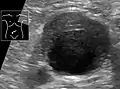

An abdominal aortic aneurysm is usually diagnosed by physical exam, abdominal ultrasound, or CT scan. Plain abdominal radiographs may show the outline of an aneurysm when its walls are calcified. However, the outline will be visible by X-ray in less than half of all aneurysms. Ultrasonography is used to screen for aneurysms and to determine their size if present. Additionally, free peritoneal fluid can be detected. It is noninvasive and sensitive, but the presence of bowel gas or obesity may limit its usefulness. CT scan has nearly 100% sensitivity for an aneurysm and is also useful in preoperative planning, detailing the anatomy and possibility for endovascular repair. In the case of suspected rupture, it can also reliably detect retroperitoneal fluid. Alternative less often used methods for visualization of an aneurysm include MRI and angiography.